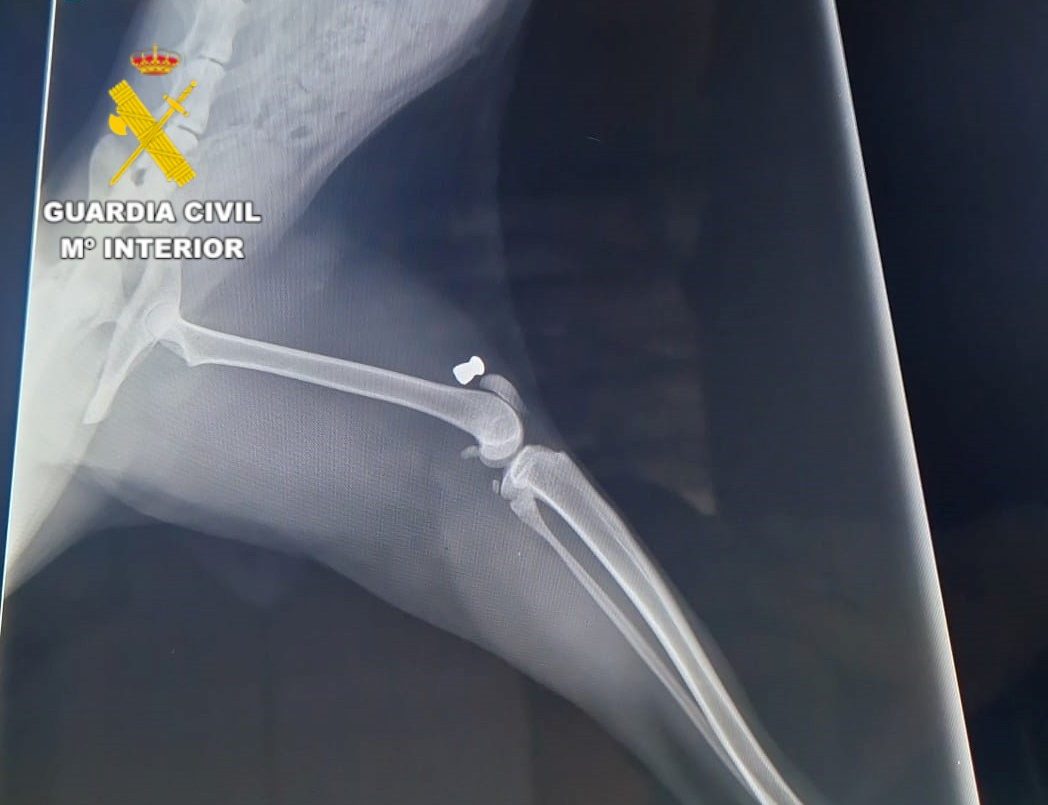

Durante el mes de septiembre, la Patrulla de SEPRONA de Segorbe inició una investigación tras ser conocedores de la muerte de tres gatos, además otros doce presentaban heridas. Durante las pesquisas obtenidas comprobaron que las lesiones eran compatibles con las producidas por impacto de perdigón de carabina de aire comprimido. Tras un examen realizado por un veterinario se confirmaron estos extremos y hallaron varios perdigones incrustados en el cuerpo de los animales.